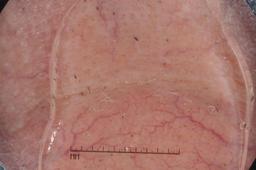

ISIC-DICM-17K (ISIC Dermoscopic Images and Clinical Metadata 17K) is a curated and balanced dataset derived from the International Skin Imaging Collaboration (ISIC) Archive Gallery. It comprises 17,060 dermoscopic images and clinical metadata (8,530 melanoma and 8,530 non-melanoma classes).

For more details, please follow the project’s GitHub repository: https://github.com/mmu-dermatology-research/isic-dicm-17k

This dataset was used in this study and benchmark to explore the effectiveness of multimodal learning for skin lesion classification:

S. Ahammed, X. Cui, W. Lu and M. H. Yap, "Skin Lesion Classification using Dermoscopic Images and Clinical Metadata: Insights from Multimodal Models," 2025 IEEE/CVF Conference on Computer Vision and Pattern Recognition Workshops (CVPRW), Nashville, TN, USA, 2025, pp. 222-230, DOI: 10.1109/CVPRW67362.2025.00027